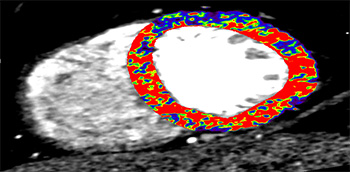

El desarrollo tecnológico ha permitido que, actualmente, la vascularización coronaria se pueda estudiar de manera no invasiva con gran fiabilidad. Entre las técnicas disponibles destaca la cardio-tomografía computarizada (CTC).

En este documento se describen las indicaciones de uso adecuado de la CTC en la cardiopatía isquémica. Se repasan las indicaciones actuales para realizar estudios dirigidos a cuantificar la calcificación coronaria y detectar estenosis coronaria y se revisan pautas sobre cómo se debe emplear la CTC en pacientes revascularizados.